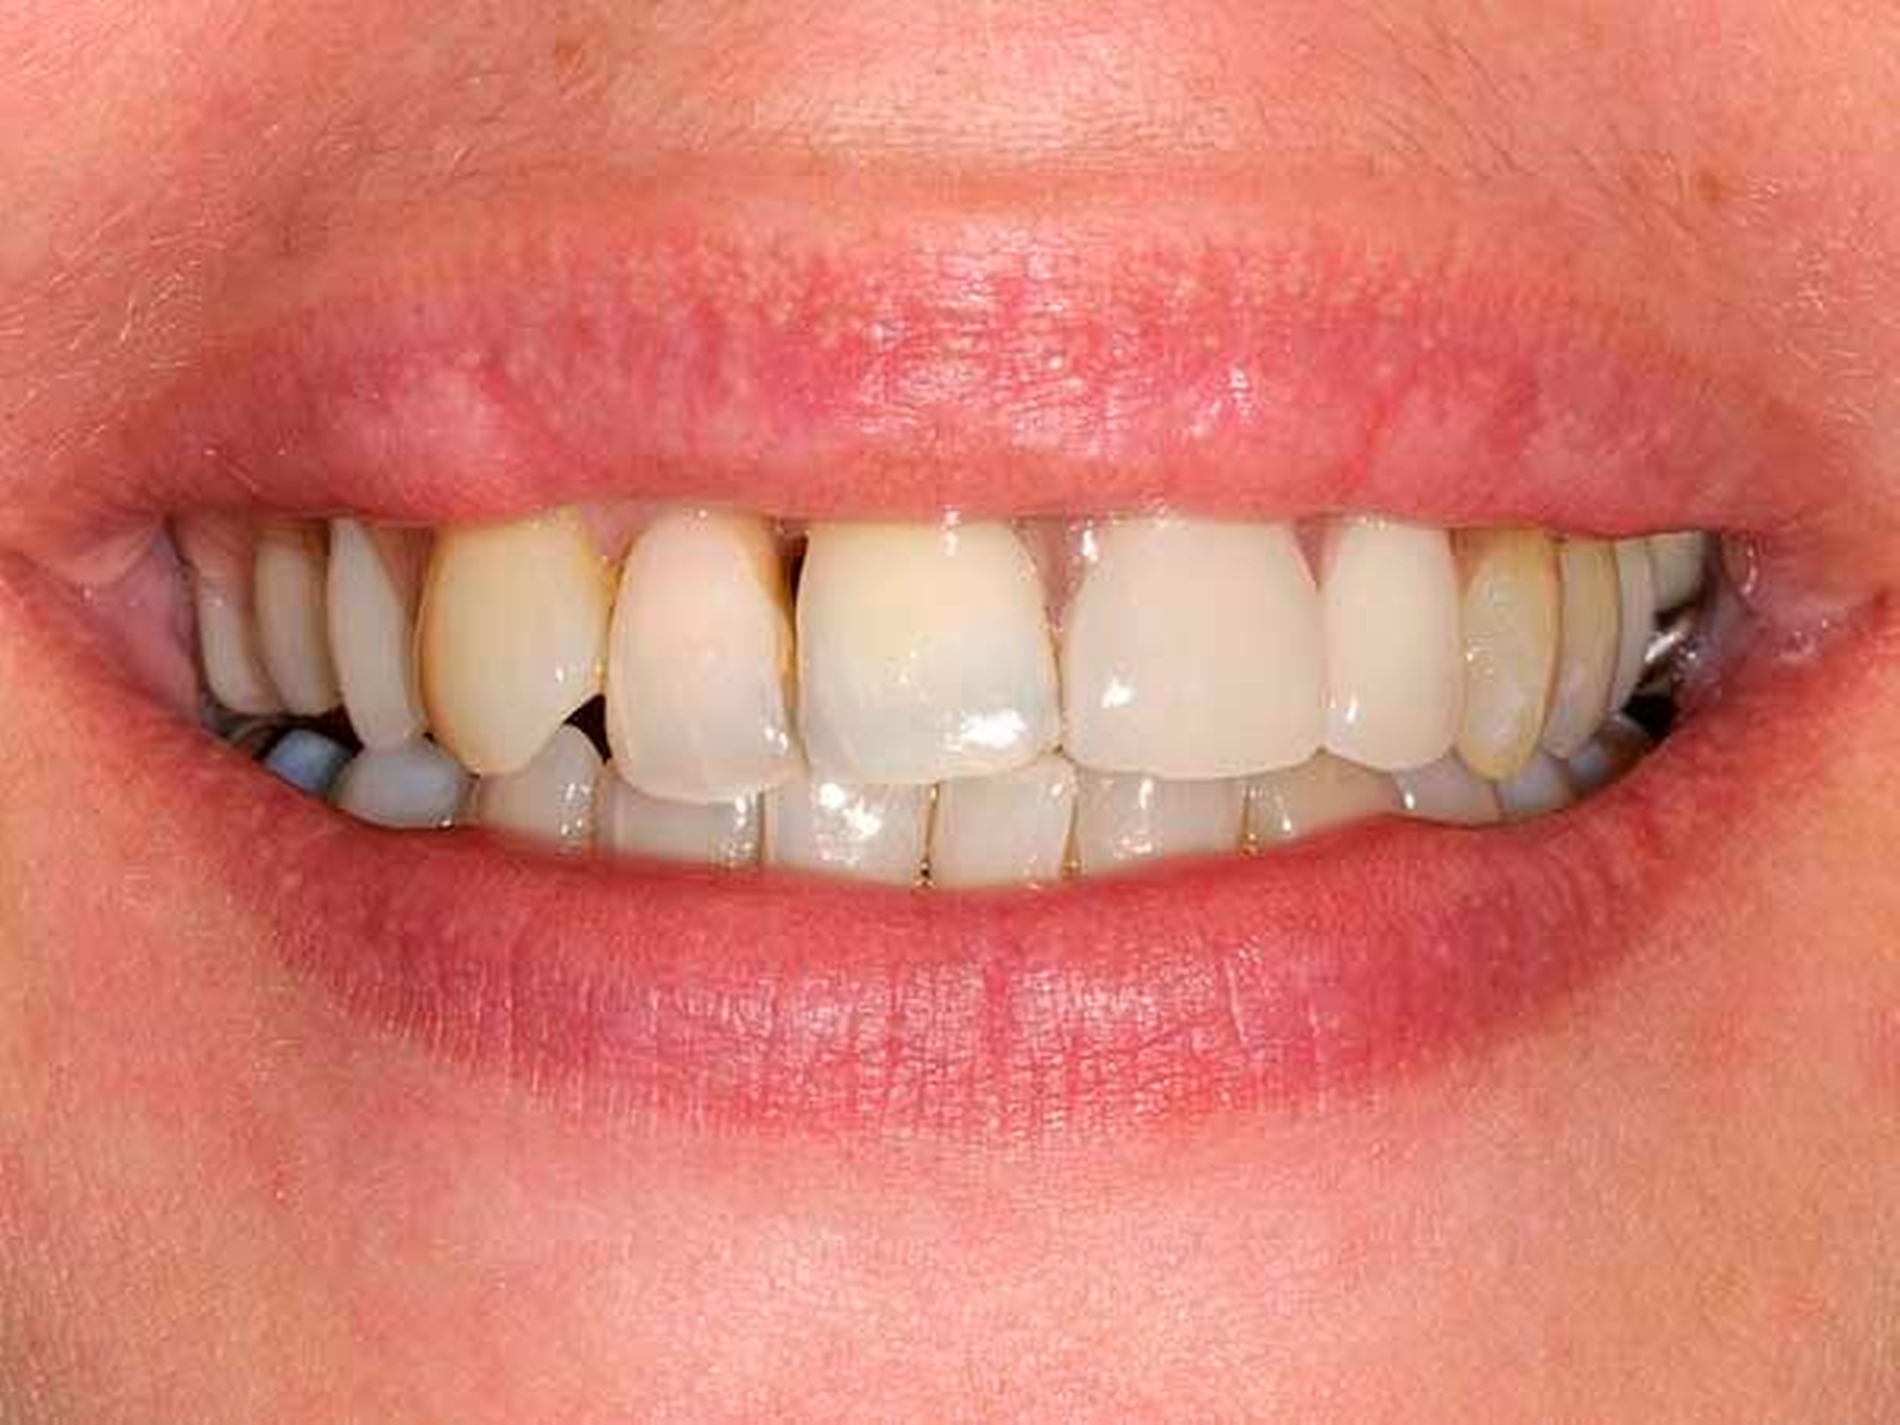

Das Orthopantomogramm (Abbildung 17) zeigt die Gebisssituation einer 49-jährigen Patientin nach Abschluss einer parodontalen Vorbehandlung. Die sehr gepflegte Patientin betreibt eine intensive Mundhygiene, legt hohen Wert auf ihre äußere Erscheinung. Ihre finanzielle Limitation lässt aber keine implantatprothetische oder aufwendige kombiniert festsitzend-herausnehmbare Versorgung zu. Da die Patientin eine hohe Lachlinie hat und eine Demaskierung durch sichtbare Gussklammern im Bereich der Frontzähne fürchtete (Abbildung 18), verweigerte sie konventionellen gussklammerverankerten Zahnersatz und trug entgegen ausdrücklichem zahnärztlichem Rat dauerhaft eine rein schleimhautgelagerte Teilprothese. Die Patientin wurde mit der Bitte um Beratung und Behandlungsübernahme an unsere Einrichtung überwiesen.

Diese Patientin konnte an unserer Einrichtung mit der Modifikation eines gussklammerverankerten Zahnersatzes versorgt werden, bei dem die anterioren sichtbaren Klammer-Retentionsarme aus dem gingivafarbenen Kunststoff Polyamid-12 (Valplast) angefertigt wurden (Abbildungen 19 und 20). Die Polyamidretentionarme müssen aufgrund des wesentlich geringeren Elastizitätsmoduls gegenüber einer CoCrMo-Legierung wesentlich breiter gestaltet werden. Sie liegen allerdings nur den vestibulären Flächen der Ankerzähne an und sind unter der partiell mitbedeckten Gingiva hohlgelegt (Abbildung 21).

Das metallische Gerüst der Teilprothese ist bis auf den Verzicht der anterioren Retentionsarme konventionell mit großem Verbinder, kleinen Verbindern, oralen Klammerarmen und Auflagen gestaltet, posterior findet eine konventionelle Ney-Klammer #1 Anwendung. Die Patientin ist mit dem ästhetischen Ergebnis zufrieden. Inzwischen konnte eine Reihe Patienten mit ähnlicher ästhetischer Problematik versorgt werden (Abbildung 22).